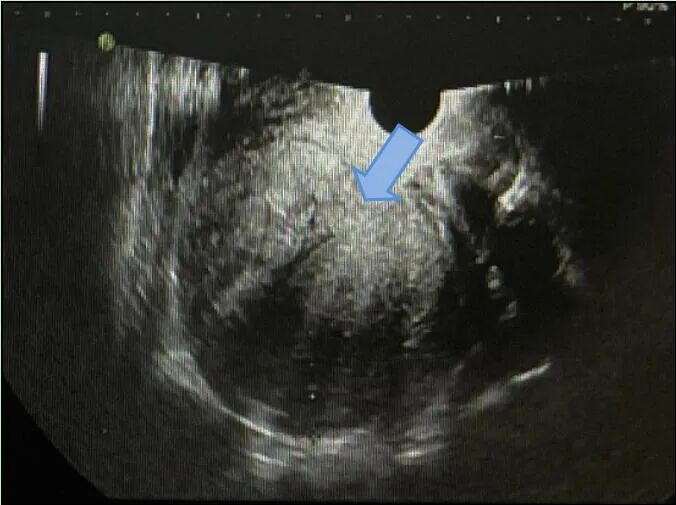

经腹超声:子宫体大小约9.0 cm×11.3 cm×11.3 cm,肌层回声不均,子宫体部可见低回声结节,大小约8.5 cm×9.8 cm×9.2 cm;CDFI示周边及内部见条状血流信号,挤压宫腔。

距首次手术后3个月,复查超声见子宫体大小约6.7 cm×7.0 cm×6.0 cm,肌层回声不均质,后壁突向宫腔见低回声,范围约2.5 cm×1.8 cm×1.6 cm;CDFI示周边及内部均可见点条状血流信号,宫腔居中,可疑子宫肌瘤复发。

距首次手术后半年,复查超声见子宫体大小约6.3 cm×7.1 cm×6.1 cm,肌层回声不均质,后壁为著,后壁突向宫腔见低回声,范围约2.2 cm×2.5 cm×1.9 cm;CDFI示周边及内部均可见点条状血流信号,宫腔受压前移,子宫内膜厚1.2 cm,回声不均。结合临床病史,考虑子宫肌瘤复发。